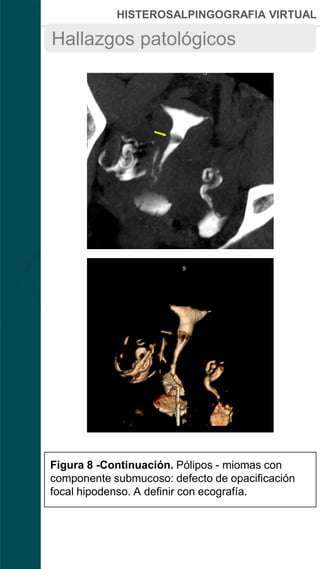

Figura 8 -Continuación. Pólipos - miomas con

componente submucoso: defecto de opacificación

focal hipodenso. A definir con ecografía.